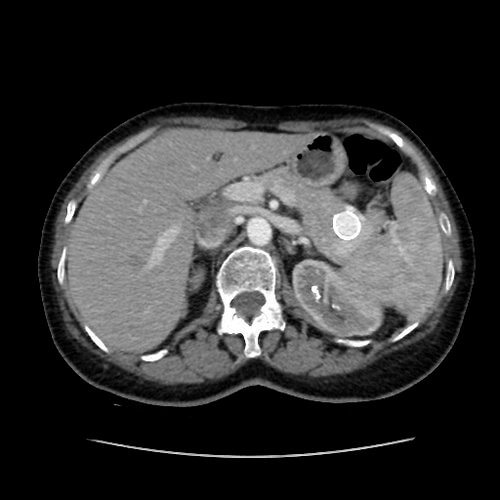

45 year old female patient who presents with ill-defined abdominal pain. A CT demonstrated a splenic artery aneurysm. Treatment was attempted from a femoral approach but the tortuosity of the splenic artery made it impossible to maintain a stable catheter position. As a result, radial access was obtained, and embolization was ultimately performed with multiple detachable coils.